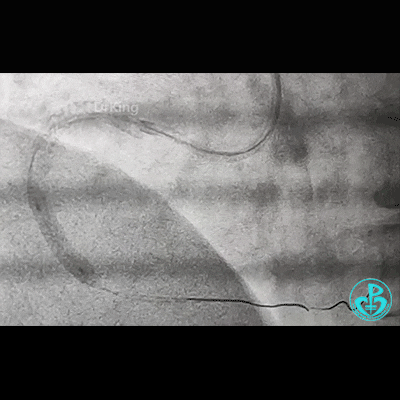

冠脉造影

右锁骨下动脉迂曲打圈,影像如下: